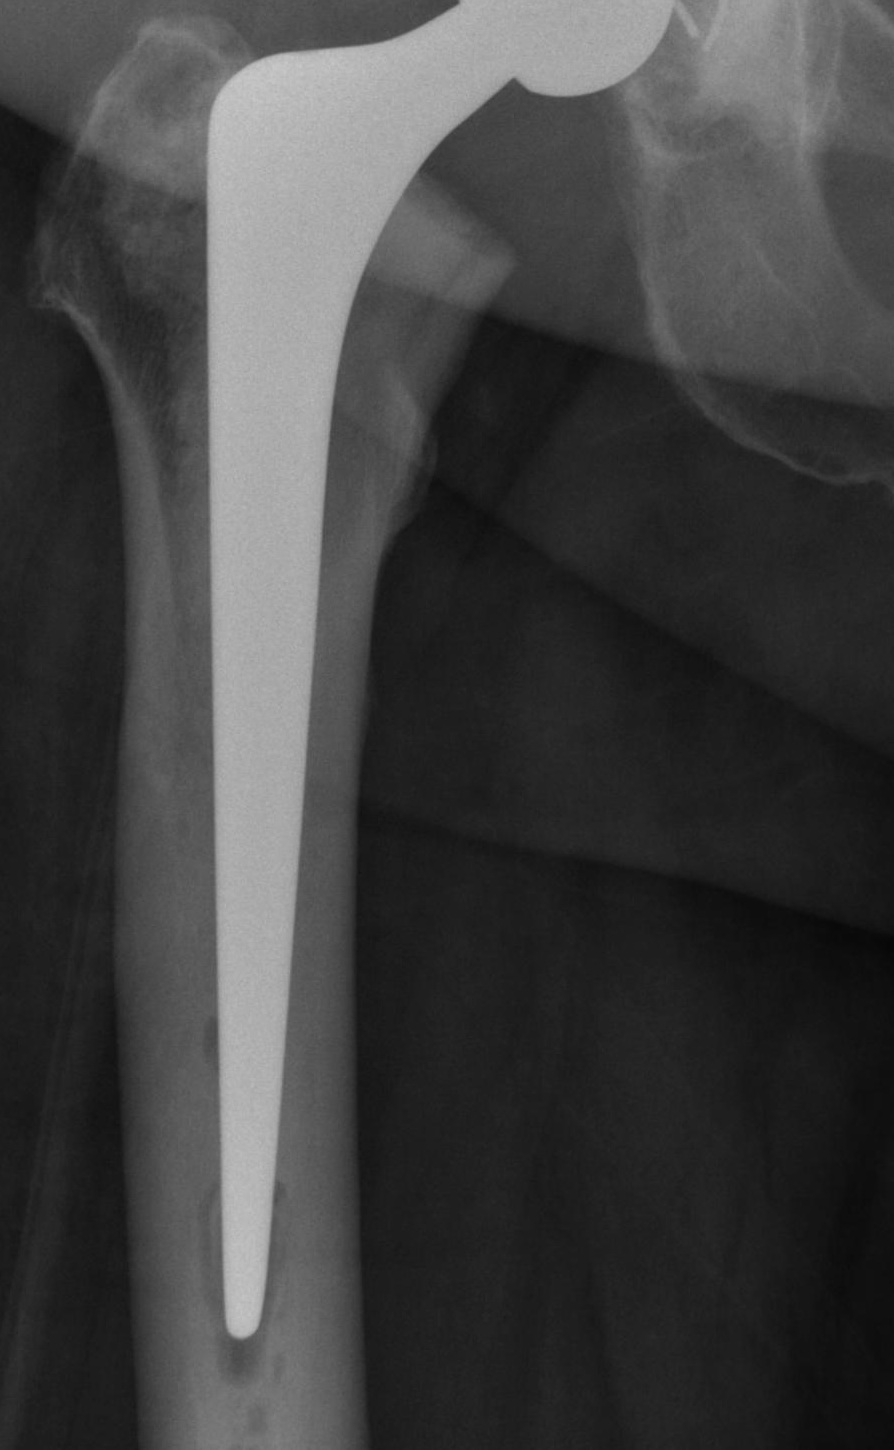

Barrack's femoral component cementation quality grading system

| Grade | Definition |

|---|---|

| A | Complete filling of the medullary canal, without radiolucent lines between the cement and the bone (white-out) |

| B | Radiolucent line covering up to 50% of the cement-bone interface |

| C | Radiolucent line covering between 50% and 99% of the cement-bone interface or incomplete cement mantle |

| D | Complete radiolucent line (100%) at the cement-bone interface and/or absence of cement distally to the end of the stem |

Grade A Grade B Grade C Grade D